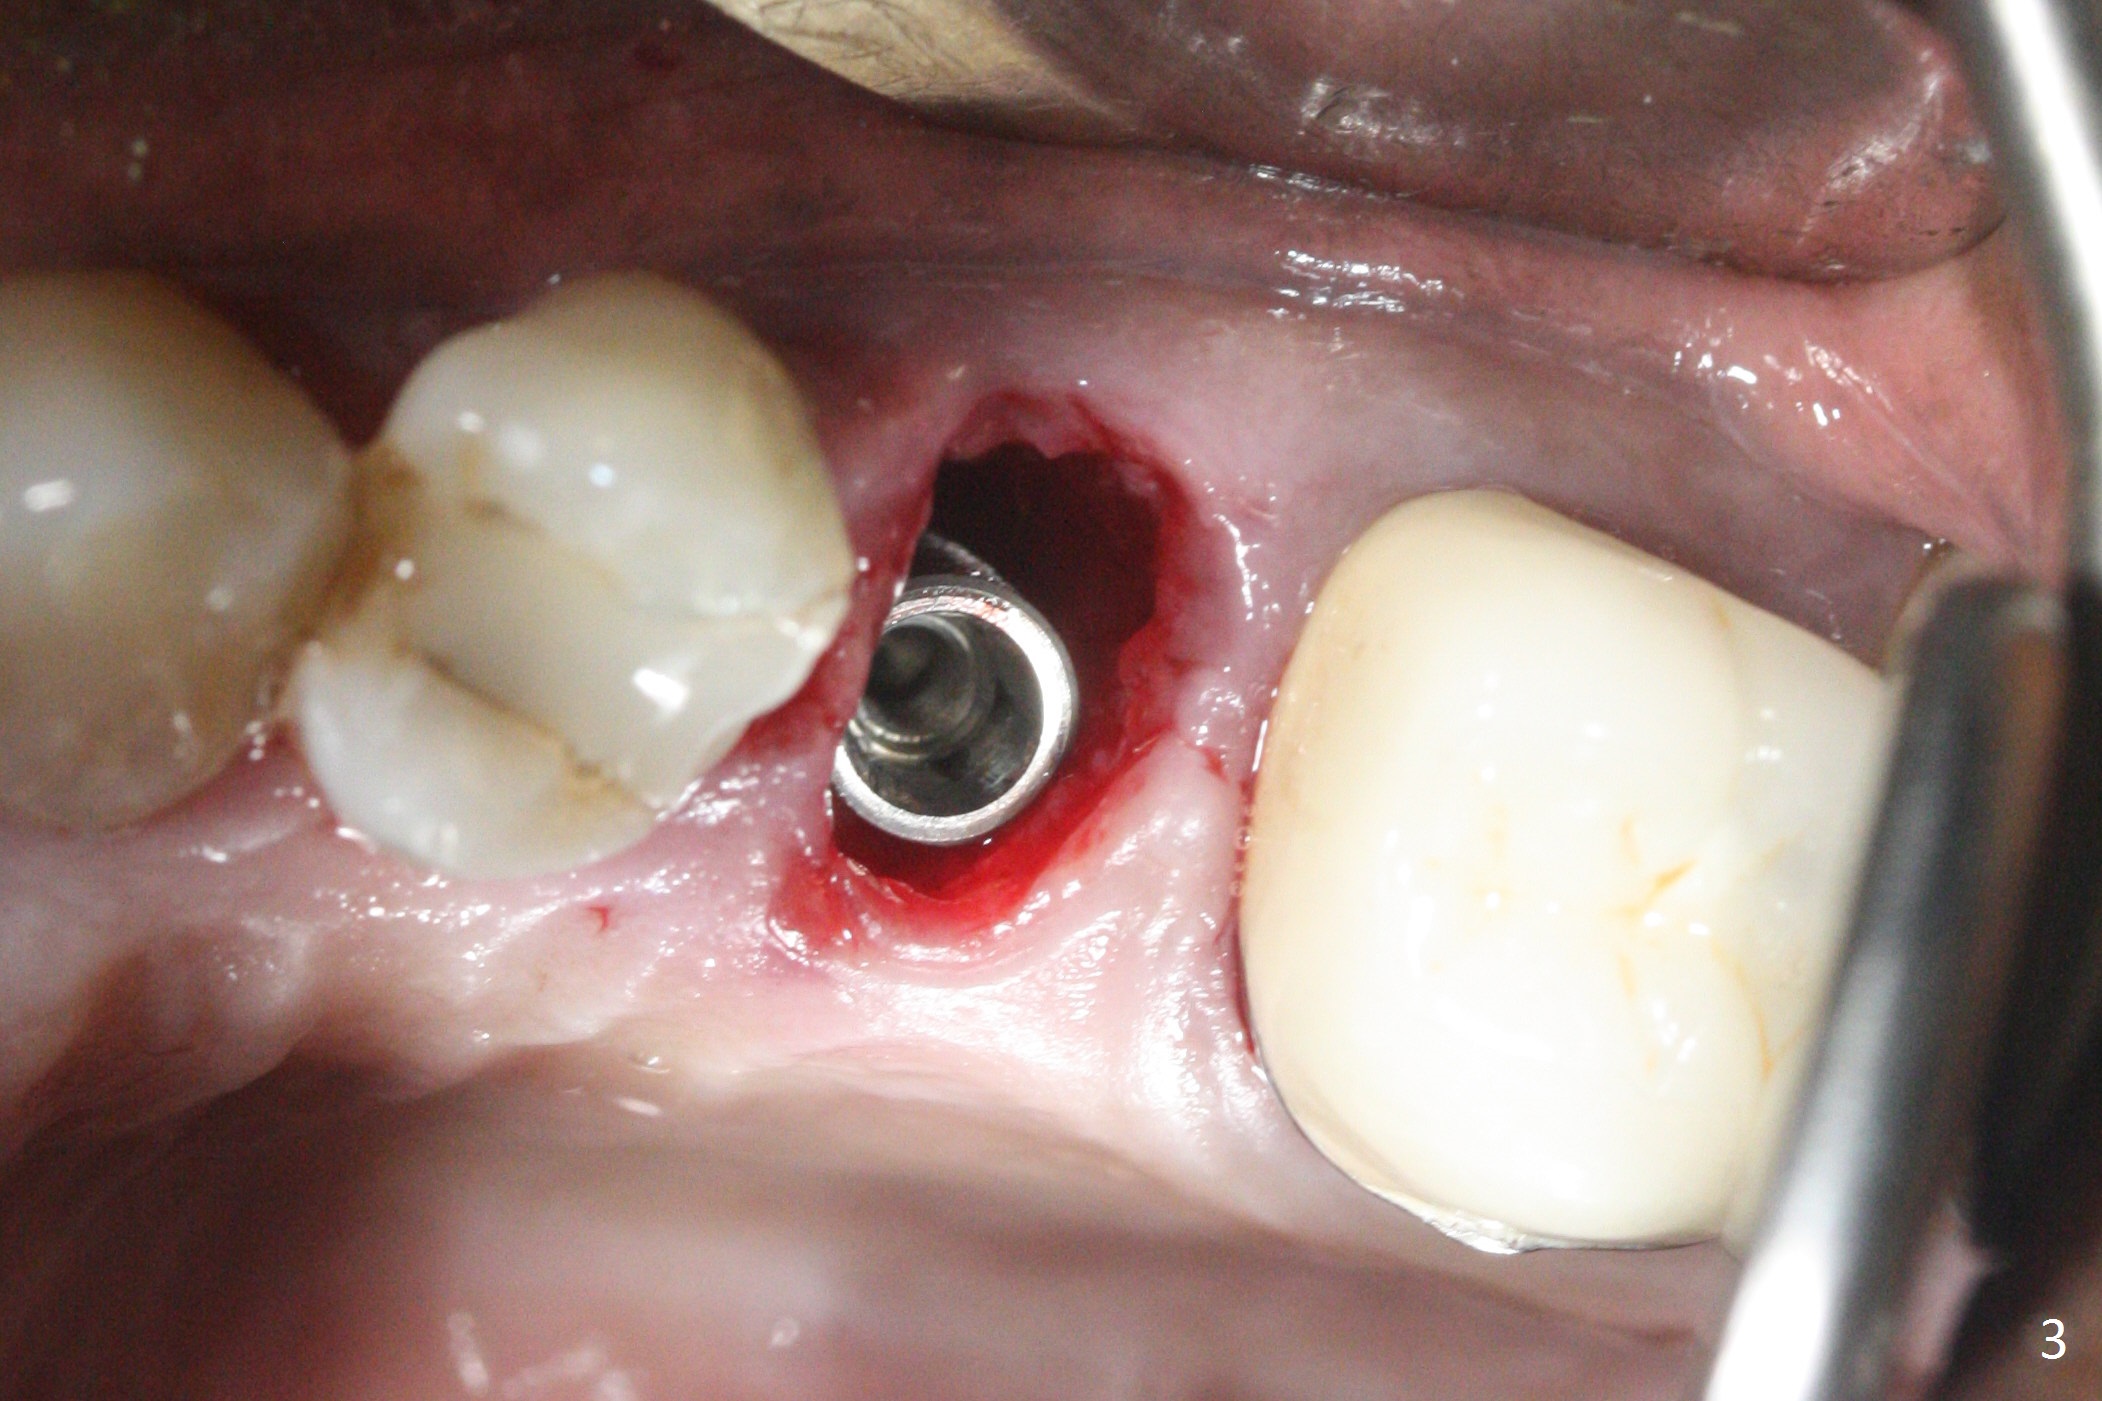

Since the apical native bone is limited at #13 after extraction, no PA is taken until a 4x11 mm dummy implant is placed after 1.6 mm and 3.3 mm drills for 13 mm (Fig.1). After using Lindamann bur to move the osteotomy distal and reusing 3.3 mm drill, the trajectory of a 4.5x11 mm IBS dummy implant improves (Fig.2,3 with low stability). When the implant is removed, the buccal portion of the socket is found to be perforated (Fig.4 P). Although the reason for the perforation is unknown, it is repaired by insertion of a piece of PRF plug, followed by allograft. #1 and 2 in Fig.4 represent the 1st and 2nd osteotomies, as shown in Fig.1 and 2, respectively. The trajectory of the final 5x13 mm implant is acceptable (Fig.5-7, different angulations), so is insertion torque (45 Ncm). After placing a 5.5x4(4) mm abutment, an immediate provisional is fabricated (Fig.8 P) with occlusal clearance (*). The interdental papillae remain in place 12 days postop (Fig.9 *). There is no sign of postop sinus infection. The provisional is loose 18 days postop; the abutment is changed to 5x4(3) mm (Fig.10). It is difficult to catch the mesial margin of the abutment for impression 4 months postop, due to poor oral hygiene and the short cuff (3 mm, Fig.11). The appointment for impression is rescheduled with emphasis on oral hygiene and no wearing the provisional for a few days prior to next appointment. Bone has grown into the space between the 1st and 2nd threads 5 months post cementation (Fig.12) and the bone is normal, solid and dense 2 years 11 months post cementation (Fig.13 >). There is mesial open margin of the tooth #14 (Fig.13,14 *).